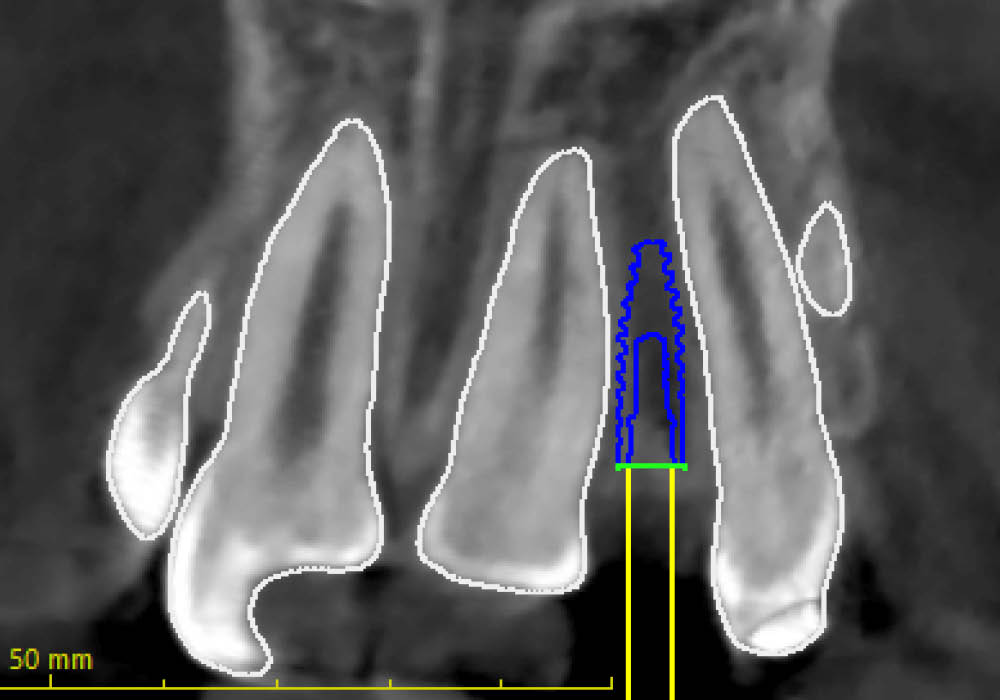

La segmentazione dei dati CBCT è stata effettuata partendo da un file DICOM.

L’utilizzo dell’intelligenza artificiale ha permesso di automatizzare la separazione e la ricostruzione tridimensionale delle strutture anatomiche, facilitando l’elaborazione e garantendo maggiore precisione nella valutazione iniziale.

La pianificazione chirurgica ha previsto un’analisi tridimensionale dettagliata del sito implantare, valutato sia da angolazioni multiple sia in visione frontale diretta.

L’obiettivo era quello di definire con precisione posizione, profondità e inclinazione dell’impianto, tenendo conto della vicinanza delle radici adiacenti e della necessità di preservare un adeguato spessore vestibolare.